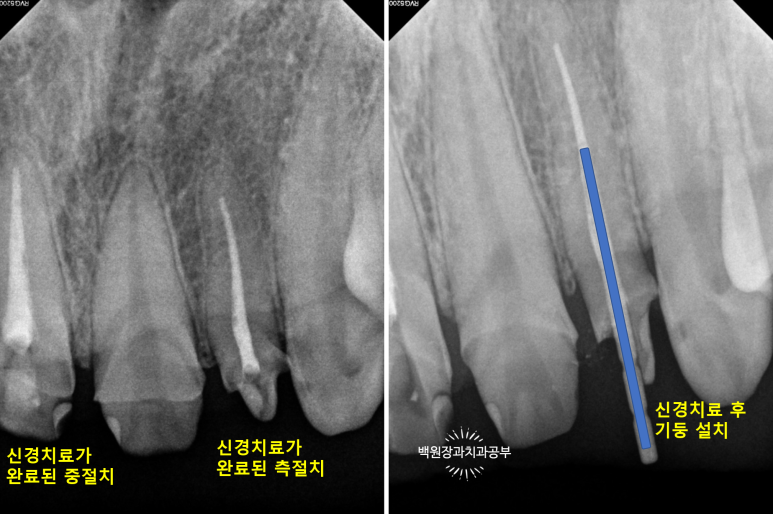

신경치료가 완료되면 해당 치아속의 재료는 방사선 사진 상 하얗게 표시되게 됩니다.

신경치료 완료 후 남은 치아가 너무 적은 경우에는 치아 내부에 기둥 (=포스트)를 설치하게 됩니다.

눈에 보이는 부분의 치아가 너무 적으니 내부에서라도 힘을 얻으려는 노력이지요.

눈으로 보는 것과 같은 위치입니다만, 엑스레이로 보았을 때 현재 위치하는 충치가 치아 내부의 신경관과 얼마나 가까이 위치하는지를 확인할 수 있었습니다.

이에 가장 충치가 심했던 측절치는 신경치료를 할 가능성이 아주 높으며 기둥을 설치해야 한다는 정보를 얻을 수 있었습니다.